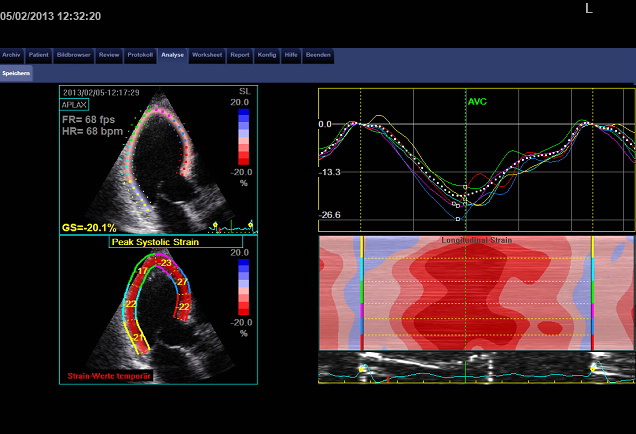

• Unsere Highlights die modernste Ultraschalluntersuchung des Herzens (Speckle tracking)

Speckle tracking